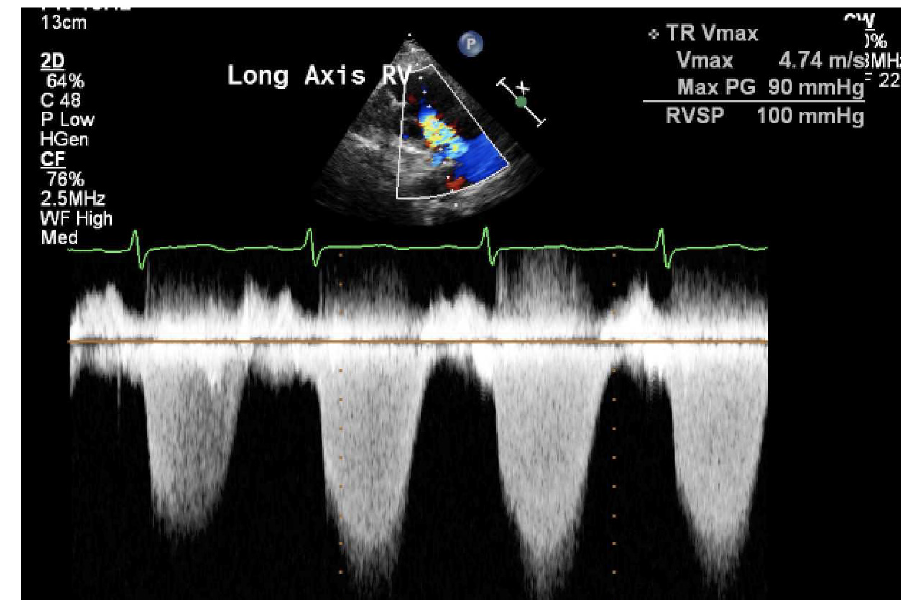

Transthoracic echocardiography showed severe dilated right chambers. There was a large, highly mobile right atrial thrombus (Figure 2), with severe systolic right ventricular dysfunction: severe tricuspid regurgitation and pulmonary artery systolic pressure of 100 mmHg (Figure 3).